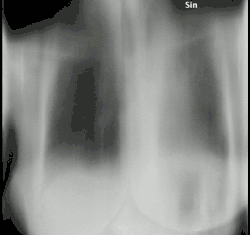

Chest